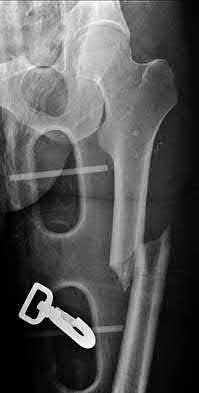

3. # Which of the following is not an appropriate implant for treatment of the fracture seen in Figure A?

5. Sliding hip screw Corrent answer: 5

The image shows a reverse obliquity intertrochanteric hip fracture.

According to the referenced article by Haidukewych et al, unstable peritrochanteric hip fractures have a worse outcome (failed in 9/16 cases) if treated with a sliding hip screw. Two additional factors that were found to have a strong correlation with postoperative failure (nonunion, loss of reduction) were poor reduction and poor implant placement. In this study, fixed angle devices were superior. Intramedullary fixation has the added advantage of a shorter lever arm and less potential for fracture collapse and limb shortening.

The IMN also acts as a medial buttress.

According to Sanders et al, the dynamic condylar screw (DCS) can also be used in subtrochanteric models, but should not be used if extensive comminution is seen, as they reported a high failure rate with DCS in these fractures if highly comminuted. They report a 77% overall union rate with this device.